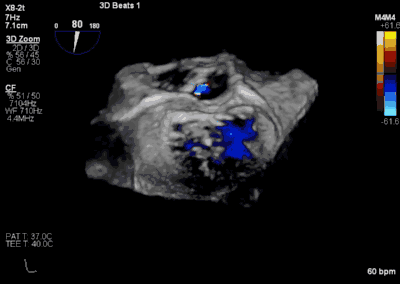

患者全麻以后,在经食道超声心动图和X射线引导下,经股静脉入路,将MitraClip瓣膜夹顺利送至二尖瓣前后叶交界中心处,成功捕捉二尖瓣前叶A2和后叶P2,经超声心动图反复确认瓣叶夹持牢固后,测定有效夹持长度10.4mm,评估反流量降至轻度,释放瓣膜夹,超声心动图评估瓣膜夹位置和功能良好,测定左房压降至26/12mmHg,再次评估反流量仍为轻度,手术顺利完成。

▲ 术后超声检查显示轻度二尖瓣反流